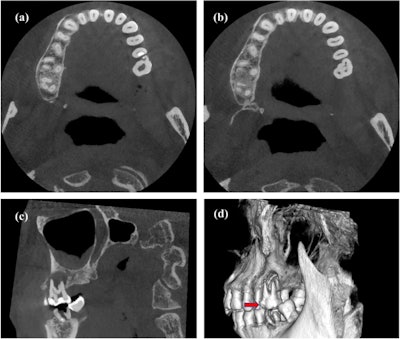

CBCT images (a, b) of the cross section of the plane of the protostylid in tooth #26. (c) The vertebral plane of the protostylid in tooth #26. (d) A 3D reconstruction of the protostylid in tooth #26. Red solid arrows indicate the protostylid.